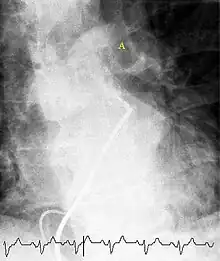

Fluoroscopic pulmonary angiography

Selective pulmonary angiogram revealing clot (labeled A) causing a central obstruction in the left main pulmonary artery. ECG tracing shown at the bottom.

Historically, the gold standard for diagnosis was pulmonary angiography by fluoroscopy, but this has fallen into disuse with the increased availability of non-invasive techniques that offer similar diagnostic accuracy.[68]